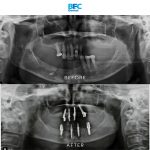

เคสรากเทียมทั้งปาก

รากเทียมทั้งปากด้วยระบบ Digital พร้อมมีฟันใหม่ได้ภายใน 1 วัน